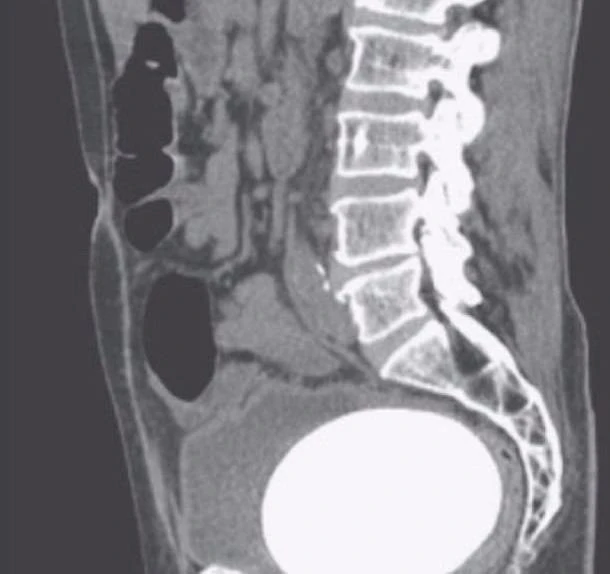

Sau khi làm các xét nghiệm cần thiết, bản quét CT đã cho thấy bệnh nhân có viên sỏi to bất thường trong bàng quang. Sau khi phẫu thuật lấy viên sỏi ra, các bác sĩ xác đinh nó nặng khoảng 770g.

Không chỉ có thế, các bác sĩ còn phát hiện viên sỏi khác nhỏ hơn trong niệu quản trái, ống dẫn nước tiểu từ thận đến bàng quang của bệnh nhân. Viên sỏi này sẽ được phá vỡ bằng phương pháp trị liệu laser.

Theo các bác sĩ, bệnh nhân  từng bị ung thư bàng quang hơn 10 năm trước và đã bị cắt bỏ bàng quang. Sau đó, người ta tạo một bàng quang giả ngoài ruột cho ông. Giống như bàng quang bình thường, túi bàng quang này kết nối với niệu đạo và niệu quản để tạo lối thoát cho nước tiểu ra ngoài cơ thể. Tuy nhiên, quá trình này có thể làm tăng nguy cơ bị sỏi.